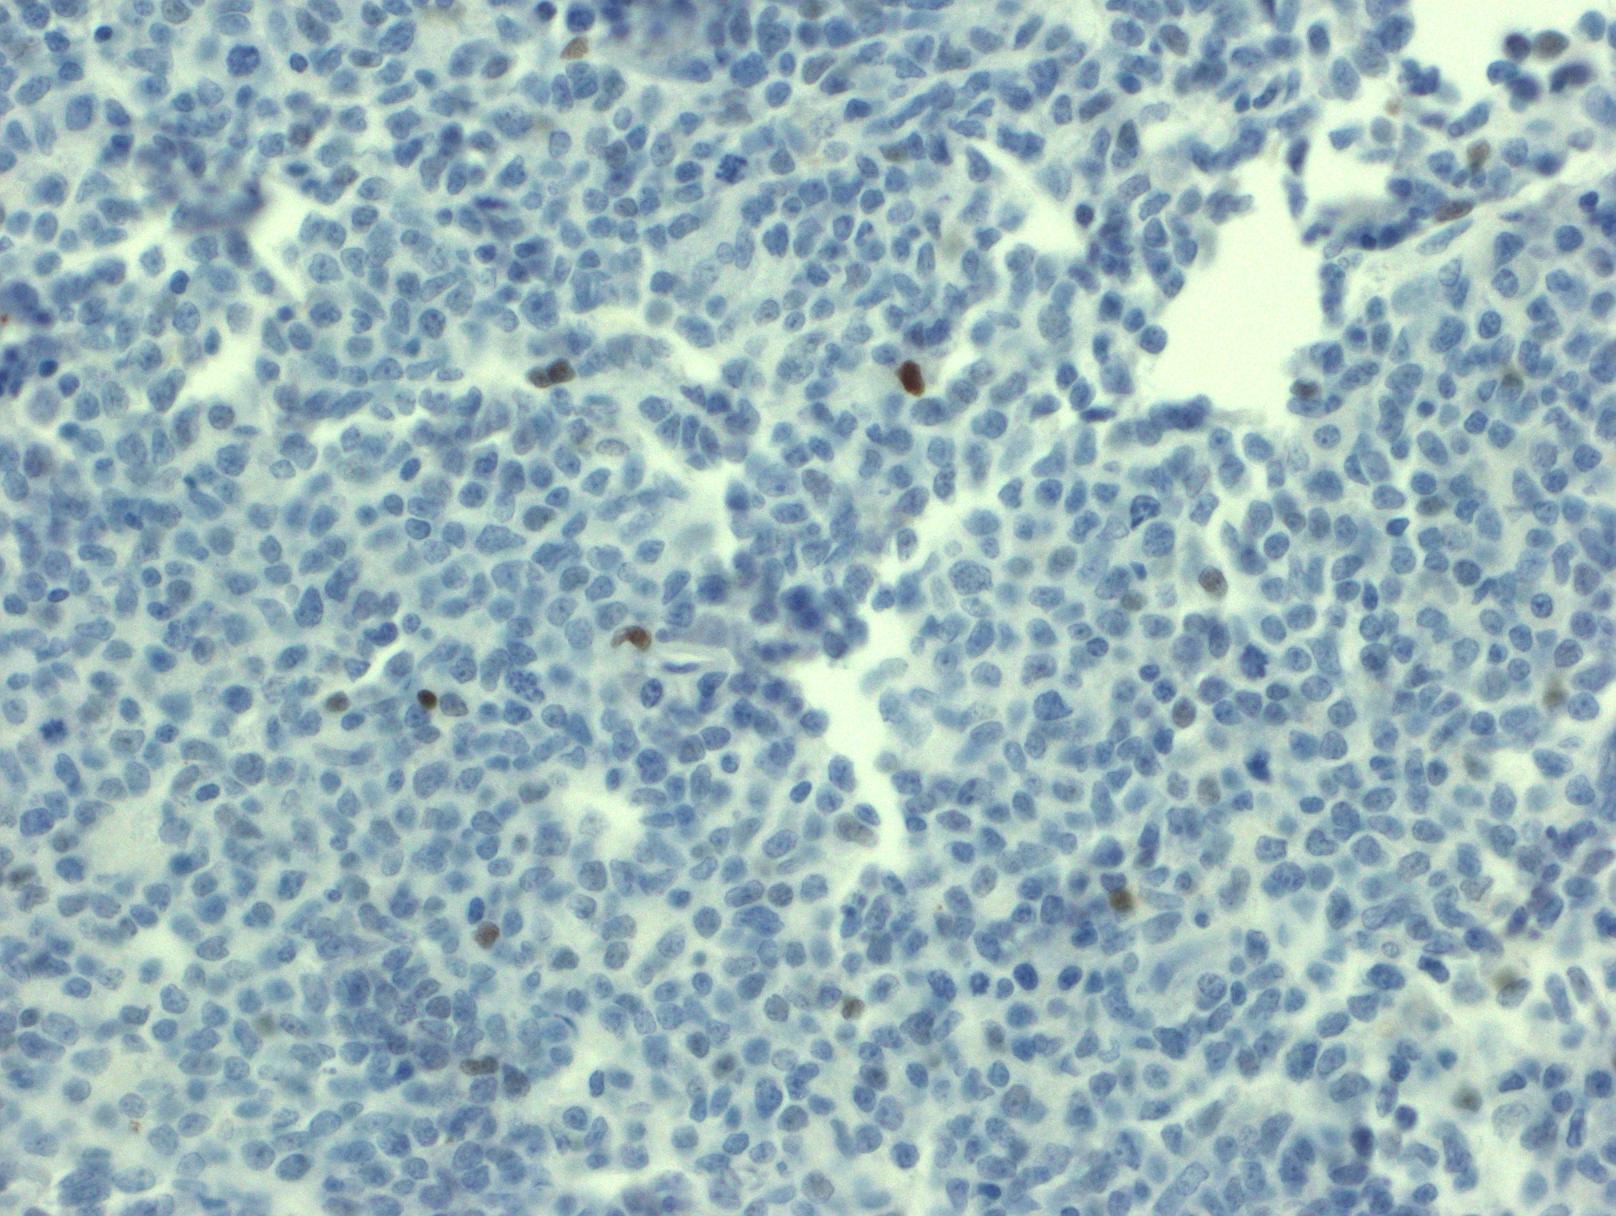

- 免疫表型: T-ALL/LBL 中淋巴母细胞呈 TdT 阳性,可表达 CD1a、CD2. CD3. CD4. CD5. CD7 和 CD8 中的一种或多种,最常见的是 CD7 和胞浆 CD3ε 阳性表达,其中只有 CD3 具有确定肿瘤细胞来源的特异性。CD4 和 CD8 常有合表达,CD10 也可以阳性;但这些都不具特异性。不成熟抗原除 TdT、CD1a、CD34 外,CD99 的表达也可表明其前体细胞的特性。部分病例表达 TAL1(核染)。偶有病例 CD117 阳性(常伴有 FLT3 突变)。10%病例表达 CD79a,少数可以表达 CD13 和/或 CD33。根据分化阶段不同,可将 T-ALL 分为以下几型:原 T(Pro-T):cCD3+、CD7+、CD2-、CD1a-、CD34-/+、CD4-、CD8-;前 T (Pre-T):cCD3+、CD7+、CD2+、CD1a-、CD34+/-、CD4-、CD8-;皮质 T(cortical T):cCD3+、CD7+、CD2+、CD1a +、CD34-、CD4+、CD8+;髓质 T(medullary T):cCD3+、CD7+、CD2+、CD1a-、CD34-、sCD3+、CD4 或 CD8 阳性。前两型中的很多病例符合 WHO 2017 年版分类中的早期前 T 淋巴母细胞白血病 (见下)。

早期前 T 淋巴母细胞白血病(early precursor T-lymphoblastic leukemia, ETP-ALL ): 此亚型仅表现出很有限的早期 T 分化,在免疫表型和遗传学上保留了某些髓系和干细胞特征。淋巴母细胞表达 CD7. cCD3, 可以表达 CD2 和/或 CD4,并表达一个或多个下列髓系或干细胞标志:CD34, CD117, HLADR, CD13, CD33, CD11b or CD65,但不表达 CD1a 和 CD8。常见下列髓系相关基因突变:FLT3, NRAS/KRAS, DNMT3A, IDH1, and *IDH2__。*典型 T-ALL 相关基因(NOTCH1 or CDKN1/2)突变则少见。经合适治疗,此型预后无特别不同。